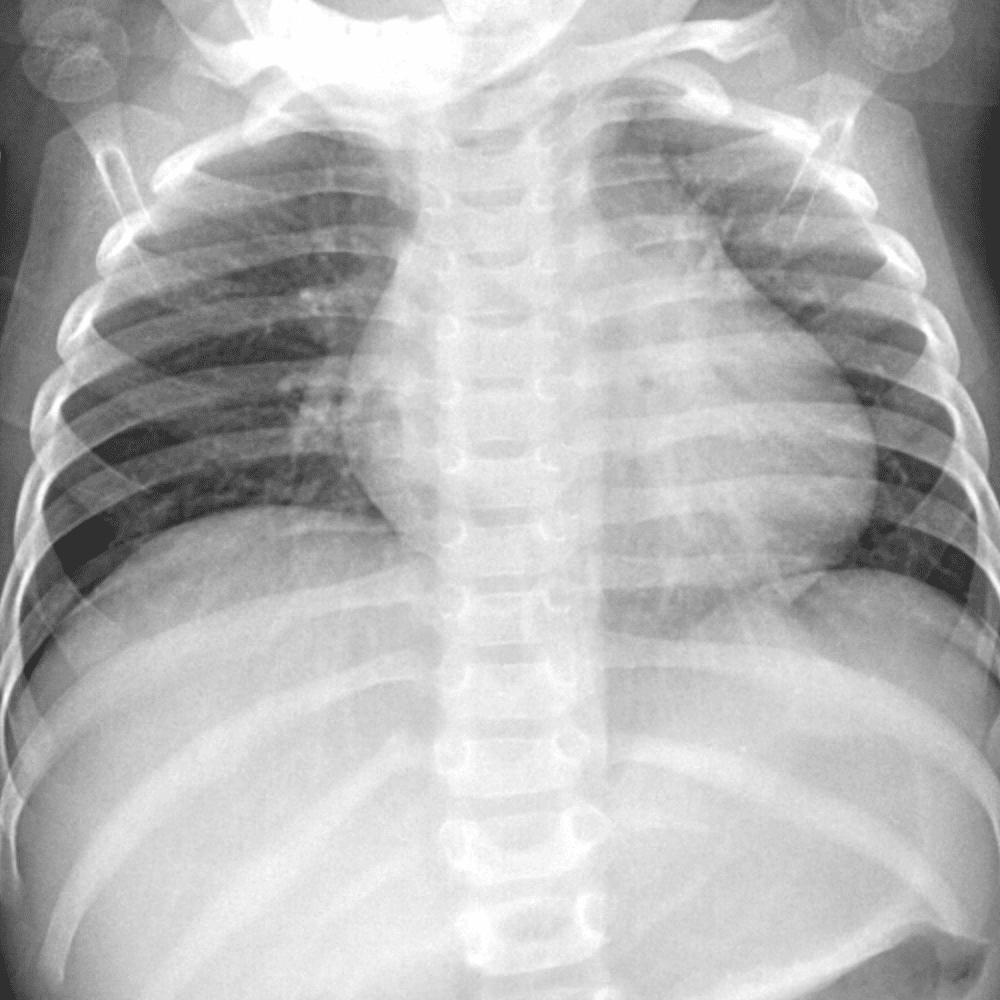

Peds Chest

Practice

Simulates call by including subtle or difficult cases and some normals.

50 cases